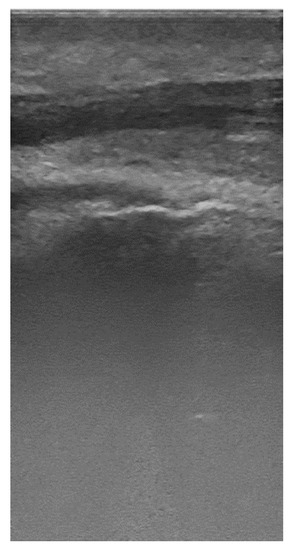

- Cropping the images and the mask to the size compatible with Mask R-CNN. Considering that the ultrasound images and the masks have 375 × 735 pixels and that the lower half part of the images do not contain useful information, the images and masks were cropped in a vertical direction and extended in a horizontal direction to a dimension of 384 × 384 pixels.